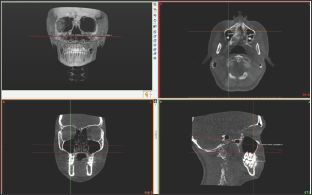

Figure 2: Determination of root apexes and placement of points.

The perpendicular distances between the root apexes and the fixed plane was measured (Figure 3). Statistical analyses were performed using IBM SPSS Statistics 20 package program (Armonk, NY: IBM Corp). A Kolmogorov-Smirnov test was used to evaluate the normality of the data. Descriptive statistics of age, gender, and the perpendicular distances between the root apexes and the fixed plane were performed. The differences according to genders were analyzed with independent t-tests, and the right and left sides of the patients were compared using a paired samples test. In our evaluations, statistical significance was set at p<0.05.

For this study, 100 patients were enrolled who had been referred to the Eskisehir Osmangazi University Faculty of Dentistry in Turkey and required a Cone Beam Computed Tomography (CBCT) examination as part of their routine examination. The CBCT images were obtained in a standing position using the CBCT machine (Planmeca Promax 3D mid, Helsinki, Finland). The exclusion criteria were craniofacial syndrome, presence of a cleft lip or palate, and impacted teeth. On the 3D images of the CBCT data in Digital Imaging and Communications in Medicine (DICOM) format, a fixed plane passing through the lowest point of the right and left infraorbital foramen with the porion was created using Simplant O&O dental software (Materialise, Leuven, Belgium) (Figure 1). The determined points were placed by checking the root apexes of the bilateral maxillary canine, premolar, and molar teeth on all three planes (axial, coronal, and sagittal). In multi-rooted teeth, the longest root was taken as reference (Figure 2).